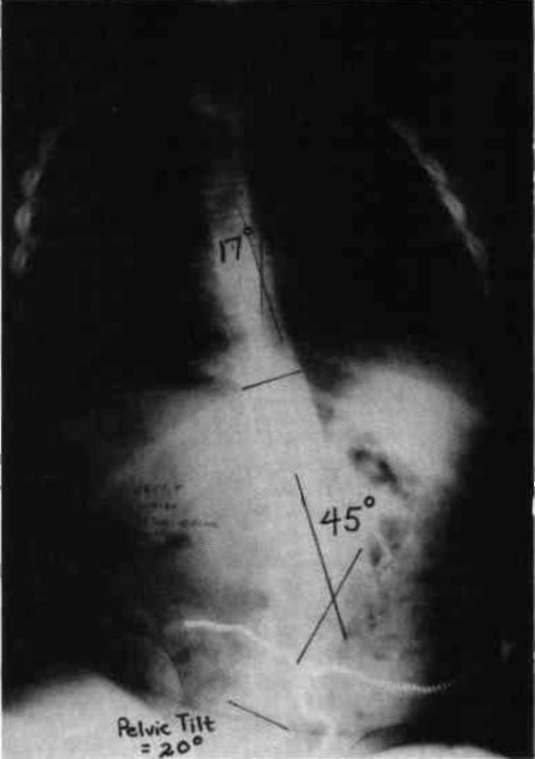

Let us now look at two examples were these stabilizing schemes have been simultaneously applied. Fig. 10a is a photo of a 12 year old boy with muscular dystrophy, sitting as he was presented to us. Fig. 10b shows the sitting support system properly applied. The corset is entirely independent; it is not attached to the seat. Fig. 10c and Fig. 10d compare his A-P spine x-rays without and with the orthotic system. The lateral tilt of his pelvis is reduced from 30 degrees to 14 degrees. The Cobb angle of his scoliosis was reduced from 65 degrees to 35 degrees. Curve control of this magnitude is not unusual as long as the deformity is still flexible. Fig. 11a is the x-ray of J.S., a 14 year old girl with cerebral palsy. She presented a right thoraco-lumbar scoliosis of 38 degrees and a rightward pelvic tilt of 8 degrees. Her shoulders were tilted 13 degrees to the left partly because she used her right arm for propping to avoid falling to the right. We provided her with a soft corset and the Gillette Sitting Support Orthosis. The Sitting Support Orthosis was to provide pelvic control and bilateral "propping" support. It had no head rest or anterior support. The x-ray taken just after fitting shows pelvic tilt reduced to 2 degrees (Fig. 11b), the Cobb angle of the scoliosis reduced to 22 degrees, and shoulders leveled. Both hands were free to function, and she said she could breathe deeper.

Figure 11a. X-ray of J.S., a 14 year old girl with cerebral palsy.

Figure 11b. J.S. provided with a soft corset and the Gillette Sitting Support Orthosis.